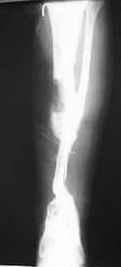

Firas,

It is difficult to see on the xr you sent, but it seems that proximal and distal metaphysis are also involved and the bone there is not of good quality too do a bifocal convergent transport.

Alternative will be to do a medial transport of half or of the all fibula after ressection of all bad quality bone as on the attached scketch.